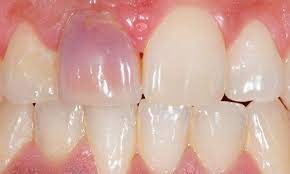

Identifying A Bruised Tooth

Most people don’t think of teeth when they think of bruises. Usually, it’s a black and blue knee versus a tooth. However, your teeth can become bruised, and it can be fairly painful. There are signs and symptoms you’ll need to be aware of, and you may need to visit the dentist depending on the severity. It may seem scary, but a bruised tooth is a common dental issue. And identifying a bruised tooth, is relatively straightforward.

CAUSES OF BRUISED TEETH

A bruised tooth is often caused by an injury to the tooth. Similar to a bruise on your skin, a bruised tooth is a reaction to excess pressure or force. While your tooth won’t turn black and blue like your skin, it can become discolored and turn a gray tint.

A bruised tooth is painful and may ache because the soft tissue and ligaments around your tooth essentially absorb the impact of the trauma or injury. Just like a bruise on your skin, the capillaries around the injured tooth burst. The capillaries then travel to the opening of the tip of the root, which gives the tooth a pinkish discoloration.

The pinkish discoloration may turn gray, which can be permanent. A gray tooth may mean that the pulp inside your tooth is impacted, resulting in a higher risk of infection or decay. This can result in the need for a root canal Brentwood. If your tooth does not turn from pink to gray, you may be in the clear. However, you should see the best dentist Brentwood has, as they will want to monitor your tooth and help you in identifying a bruised tooth.